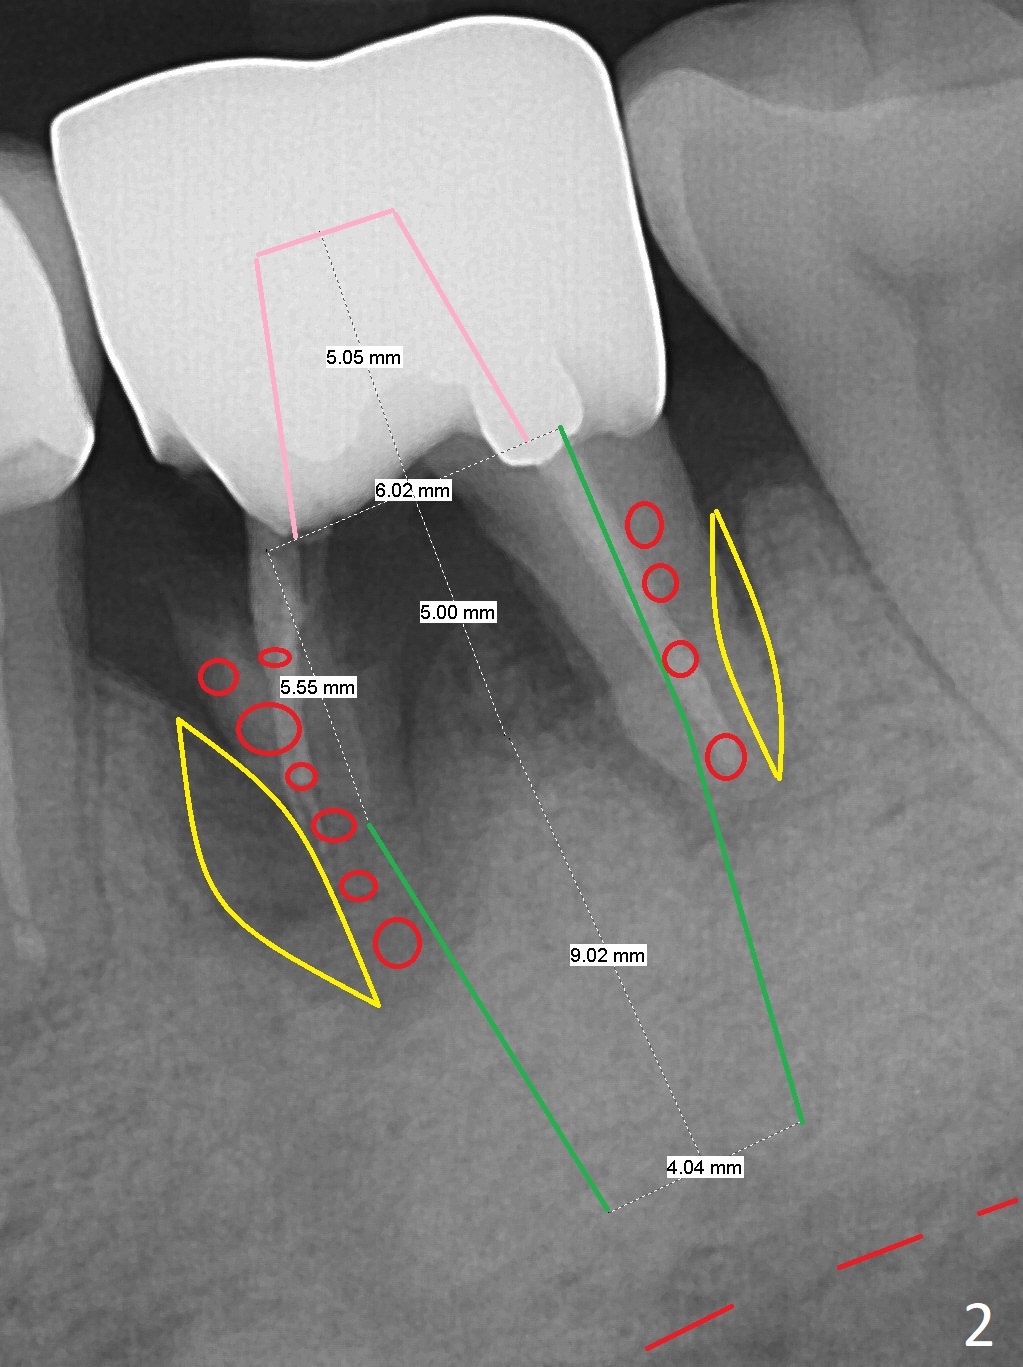

A 64-year-old man will return for #19 extraction and implant. Use IS drills with 10 mm stoppers until 4.5 mm, followed by 5x17 mm tissue-level tap (14 mm gingival level) and PA. Make sure that tap and later implant threads are in the bone or can at least be covered by bone graft (Fig.2,3).